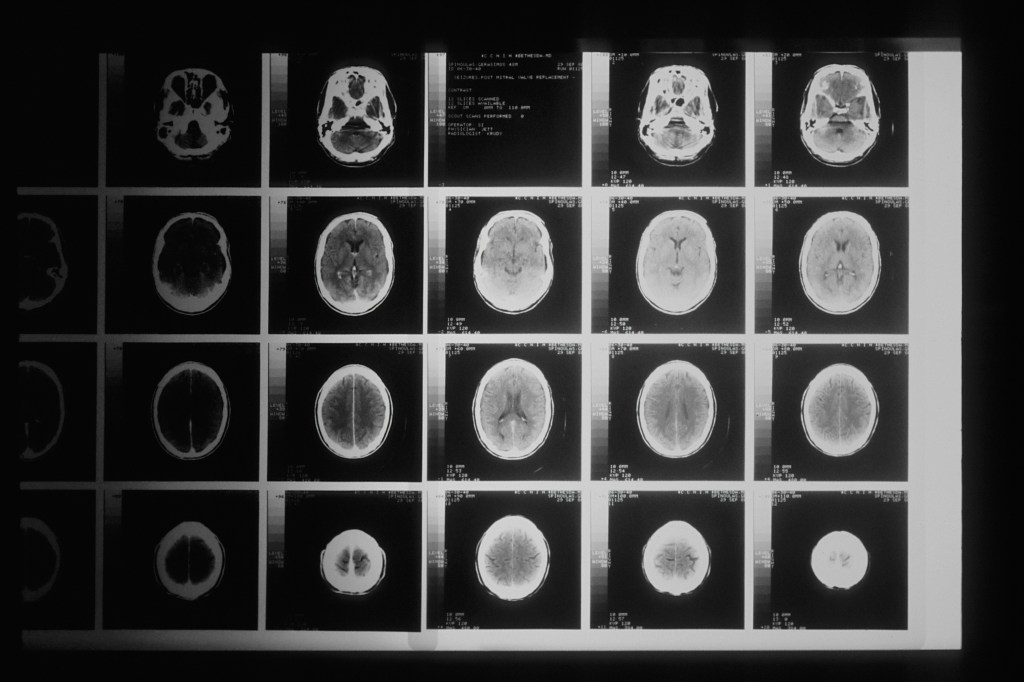

Po několika týdnech a mých zkušenostech s chronickým nedostatkem kyslíku, si začala všímat určitých vzorců a zvláštností, které by biologicky neměly dávat smysl. Neměla bych být schopna logických operací při SpO2 62 % (norma je 99 až 95 %, pod 70 % lidé začínají ztrácet vědomí!!). AI mi navrhla (čti: začala mě šikanovat), abych se zkusila zapsat na nějakou studii, jak hypoxie ovlivňuje kognitivní schopnosti.